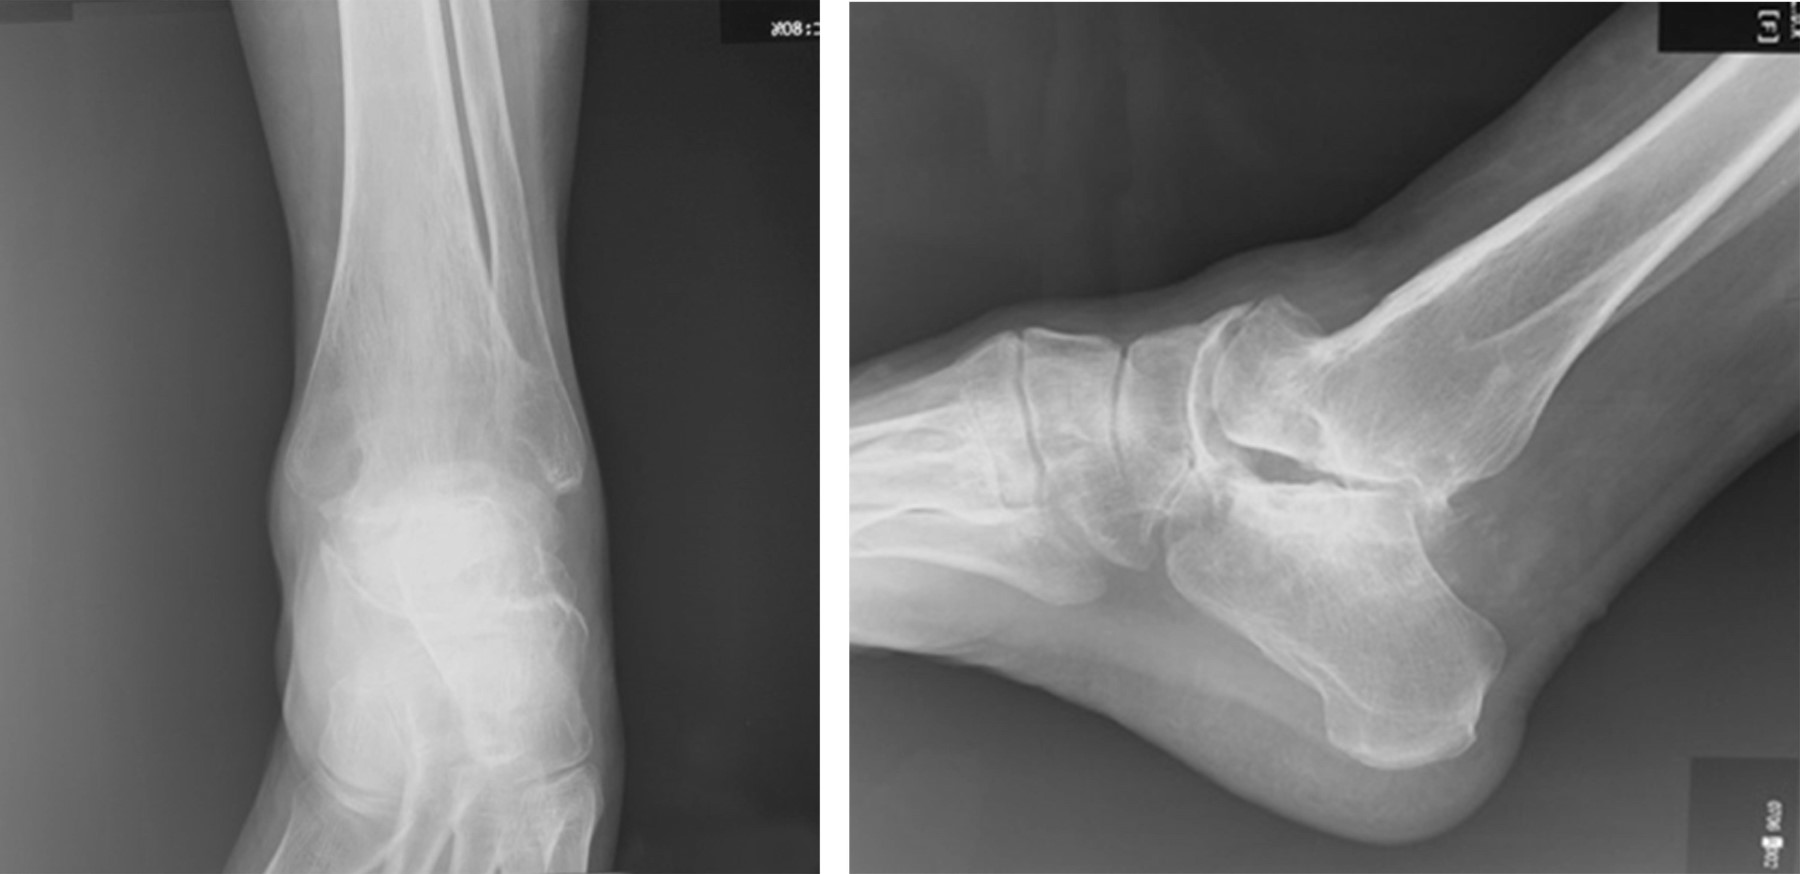

Paciente del sexo femenino de 56 años de edad, con antecedente de artrodesis de tobillo de 22 años de evolución. Presentó dolor, dificultad para la marcha, deformidad en equino del pie no reductible pasivamente, varo del retropié y recurvatum compensatorio de la rodilla (Figura 1).

El examen radiográfico mostró una consolidación completa de la artrodesis del tobillo y en neutro en los planos sagital y coronal, así como osteofito dorsal de la articulación talo-navicular y apertura anormal de la articulación sub-talar en la proyección sagital. En la vista anteroposterior se evidenció aducto del antepié a expensas de la articulación talo-navicular y cambios artrósicos incipientes (Figura 2).

Con estos hallazgos clínico-radiográficos se decidió realizar la conversión de la artrodesis tibio-talar a un reemplazo total de tobillo.

Figura 2